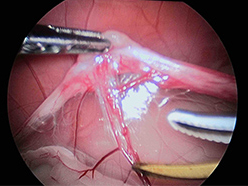

この子は肝臓の数値が高かったため、肝臓の観察と生検を避妊手術と同時に実施しました。

超音波メスにて卵巣動静脈を凝固・切開中です。

切開後の出血はまったくありません。